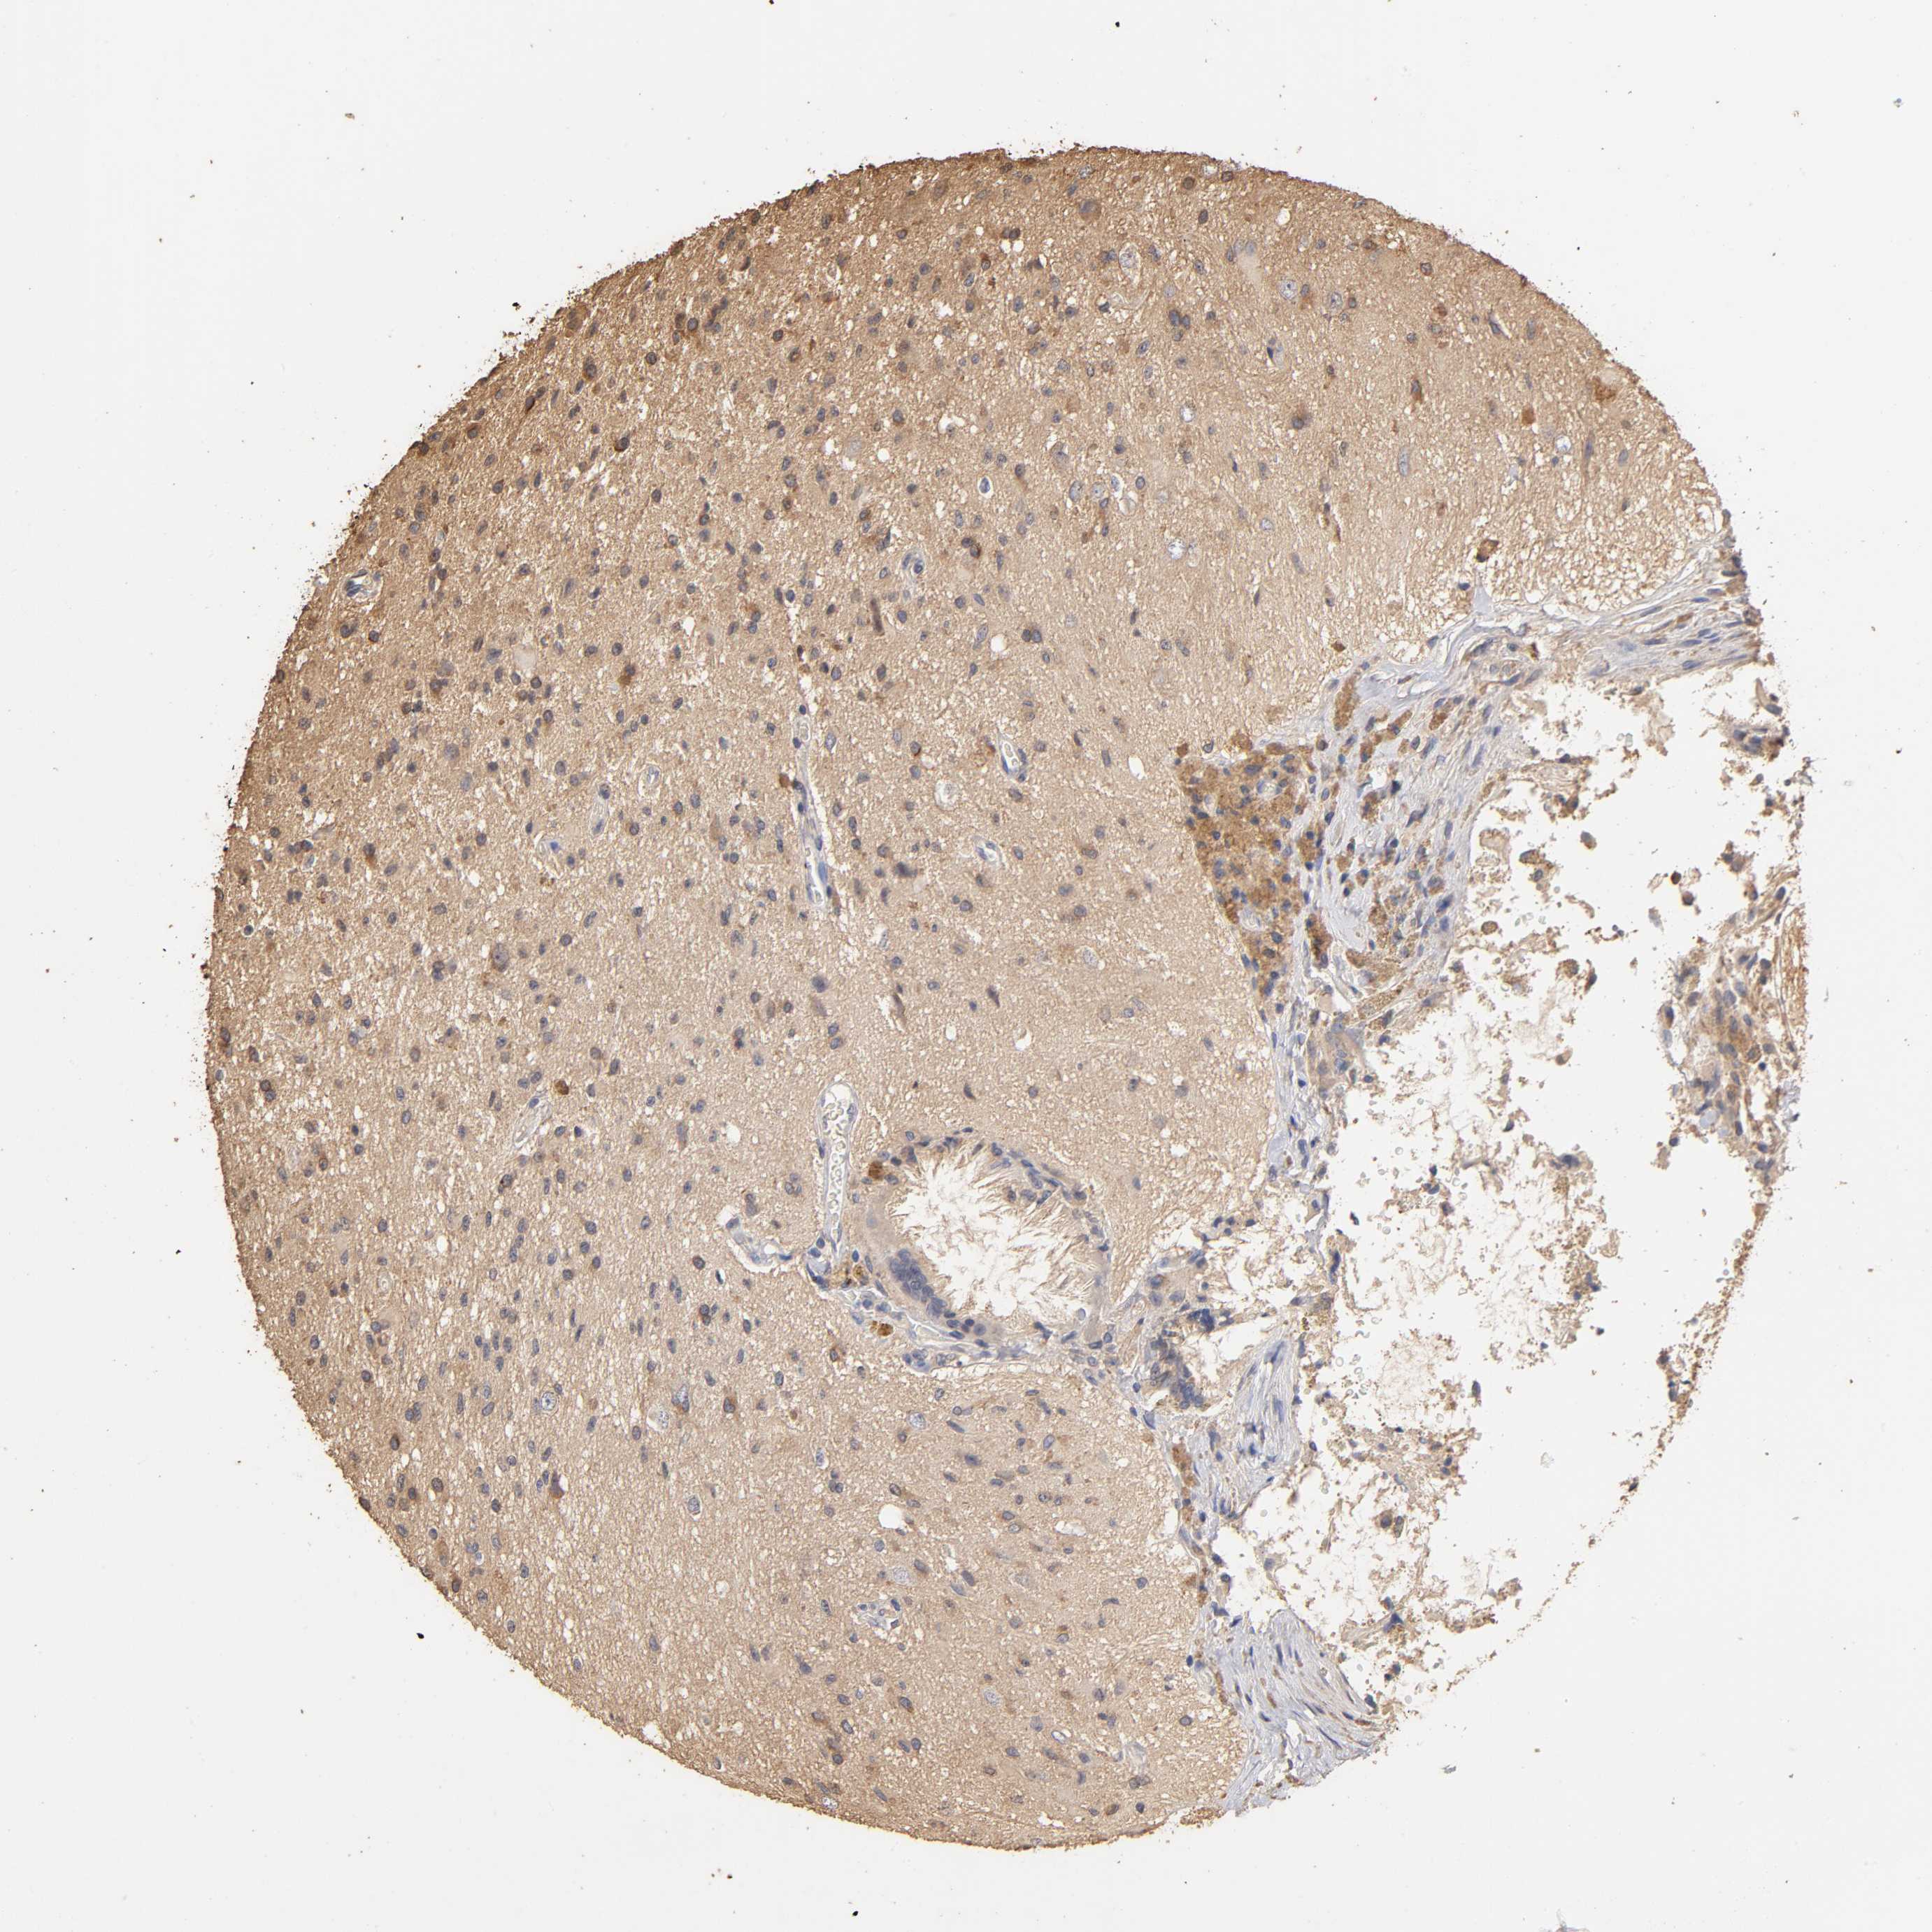

GLIOMA - Protein expressioni

A mouse-over function shows sample information and annotation data. Click on an image to view it in a full screen mode. Samples can be filtered based on level of antibody staining by selecting one or several of the following categories: high, medium, low and not detected. The assay and annotation is described here.

Note that samples used for immunohistochemistry by the Human Protein Atlas do not correspond to samples in the TCGA dataset.

Antibody stainingi

Antibody staining in the annotated cell types in the current human tissue is reported as not detected, low, medium, or high, based on conventional immunohistochemistry profiling in selected tissues. This score is based on the combination of the staining intensity and fraction of stained cells.

Each image is clickable and will lead to virtual microscopy that enables deeper exploration of all samples and also displays staining intensity scores, fraction scores and subcellular localization as well as patient and tissue information for each sample.

Antibody HPA003903

Antibody HPA072756

Antibody CAB026000

Staining

High

Medium

Low

Not detected

Intensity

Strong

Moderate

Weak

Negative

Quantity

>75%

75%-25%

<25%

None

Location

Nuclear

Cytoplasmic/membranous

Cytoplasmic/membranous,nuclear

Glioma, malignant, High grade

Glioma, malignant, NOS

Glioma, malignant, Low grade